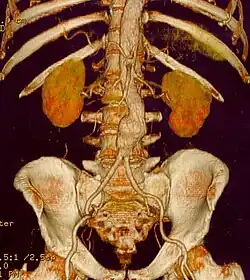

Abdominal

Abdominal aortic aneurysms (AAAs) are more common than their thoracic counterpart. One reason for this is that elastin, the principal load-bearing protein present in the wall of the aorta, is reduced in the abdominal aorta as compared to the thoracic aorta. Another is that the abdominal aorta does not possess vasa vasorum, the nutrient-supplying blood vessels within the wall of the aorta. Most AAA are true aneurysms that involve all three layers (tunica intima, tunica media and tunica adventitia). The prevalence of AAAs increases with age, with an average age of 65–70 at the time of diagnosis. AAAs have been attributed to atherosclerosis, though other factors are involved in their formation.[7]

The risk of rupture of an AAA is related to its diameter; once the aneurysm reaches about 5 cm, the yearly risk of rupture may exceed the risks of surgical repair for an average-risk patient. Rupture risk is also related to shape; so-called "fusiform" (long) aneurysms are considered less rupture-prone than "saccular" (shorter, bulbous) aneurysms, the latter having more wall tension in a particular location in the aneurysm wall.[9]

Before rupture, an AAA may present as a large, pulsatile mass above the umbilicus. A bruit may be heard from the turbulent flow in the aneurysm. Unfortunately, however, rupture may be the first hint of AAA. Once an aneurysm has ruptured, it presents with classic symptoms of abdominal pain which is severe, constant, and radiating to the back.[9]

The diagnosis of an abdominal aortic aneurysm can be confirmed by the use of ultrasound. Rupture may be indicated by the presence of free fluid in the abdomen. A contrast-enhanced abdominal CT scan is the best test to diagnose an AAA and guide treatment options.[10]